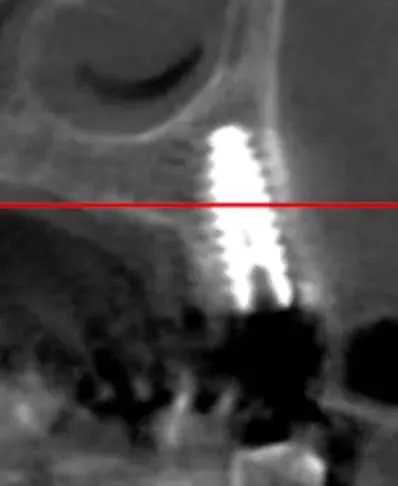

La CBCT intraoperatoria ha confermato la corretta posizione tridimensionale degli espansori e il raggiungimento della corticale del pavimento del seno in zona 2.5. In caso di dubbi sulla posizione e nel corso di interventi delicati come questo, questo ausilio strumentale è di fondamentale importanza. Ma non è sempre necessaria. L’esposizione, per quanto contenuta, dev’essere sempre ridotta al minimo, compatibilmente con la sicurezza chirurgica.

Sezione espansore sito 2.5

Espansore in posizione 2.5 con sollevamento della corticale del pavimento del seno

CBCT Post-op: Impianto in posizione 2.5 infracrestale con sollevamento della corticale del pavimento del seno